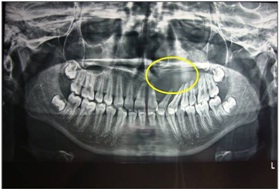

OPG confirmed our diagnosis and supplemented by showing deviation of 23,24 in order to accommodate the radiolucent mass which was a typical finding in present case [Table/Fig-5]. On performing Fine Needle Aspiration Cytology (FNAC) it showed straw coloured fluid was collected and cytology confirmed presence of paucicellular cells like polymorphs, macrophages and few squamous epithelial cells. CT scan in axial and coronal view suggested radiolucent growth in relation to left side of maxilla involving 21,22,23,24 [Table/Fig-6].

An orthopentogram showing radiolucency in relation 21,22,23,24